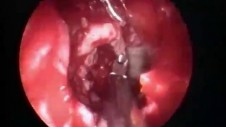

Inverted Papilloma of Septum Part 1 of 2

Inverted Papilloma of Septum Part 2 of 2